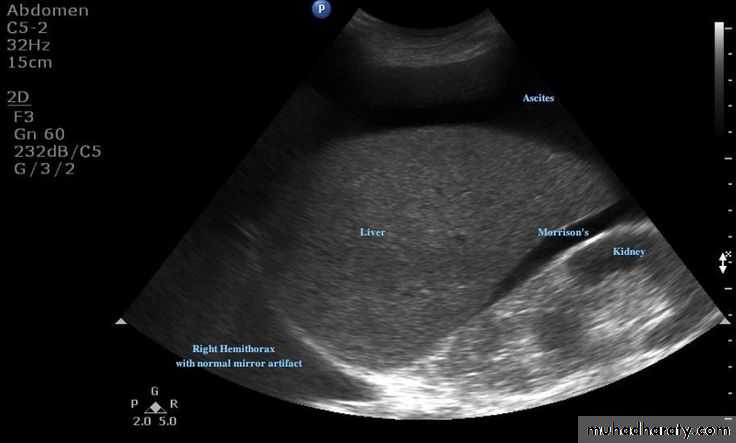

Ascites